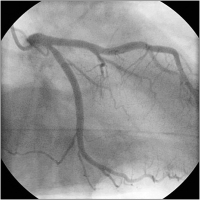

Transmurale Ischämie - Erstickungs-T-Wellen

Abbildung 4: Akutangio vor PCI